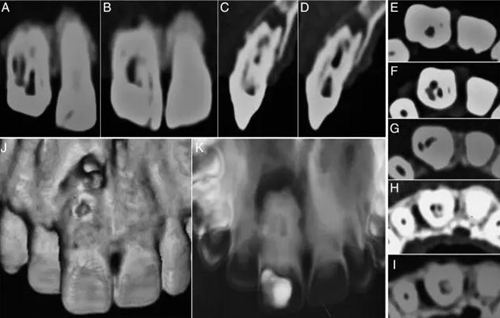

在討論完治療風(fēng)險(xiǎn)和成本等相關(guān)事項(xiàng)后患者簽署了知情同意書。橡皮障隔離,局部麻醉下開放髓腔,去除齲壞和腐爛的牙體組織。在清洗完冠部通道后用牙髓探針DG16來定位根管口。逐漸去除牙膠的同時用3%次氯酸鈉沖洗(圖1C)。隨后在釉牙骨質(zhì)界附近發(fā)現(xiàn)了兩個主要根管開口,并用手用擴(kuò)孔挫2、3和4擴(kuò)大。用10#和15#k銼探索直到遇到阻礙。用17%EDTA和3%次氯酸鈉沖洗。在初步?jīng)_洗和暫封后,病人拍攝了CBCT,顯現(xiàn)了牙體內(nèi)部形態(tài)的3維結(jié)構(gòu)(2A–K)。復(fù)診在牙科顯微鏡下探查根管,發(fā)現(xiàn)近中根管口通向一個寬的Oehlers III型b的牙內(nèi)陷(MI)。遠(yuǎn)中根管口通向2個根管,近遠(yuǎn)中根管(DM)根管和遠(yuǎn)中根管,還有一個在最遠(yuǎn)中部分的盲袋。盲袋是Oehlers II型的第二類牙內(nèi)陷(DI),因?yàn)樗K止在根中1/3。此外,還發(fā)現(xiàn)了近中切角處一個近中根管(M) (圖3A and B)。一共發(fā)現(xiàn)了5個根管并且他們之間互有交通。所有的根管除了DI都終止于一個大口徑的根尖孔。因此,牙齒被診斷為雙重牙內(nèi)陷,包含Oehlers III型b和II型。牙髓根尖周病變被診斷為慢性根尖膿腫。

圖2:A:腭部近中到遠(yuǎn)中可以看到兩個根管(MI和D)和一個盲袋;B:唇部可以看到另外兩個根管(M和DM);C和D:矢狀面可以看到環(huán)形的牙內(nèi)陷;E:寬髓室和窄M根管;F:4個根管,分別命名為M、MI、DM、D;G:盲袋DI;H:根尖有兩個根管口;I:大口徑根尖孔;J:3維上頜牙弓唇部形態(tài);K:牙內(nèi)陷腭部形態(tài)。